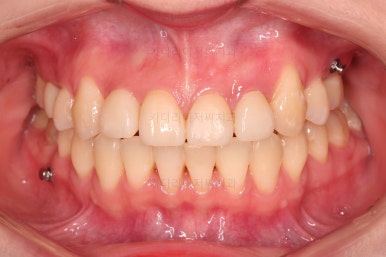

앞니 심미보철까지 마무리 되었습니다.

부산교정 전후 비교해 볼게요.

양호했던 입매는 거의 그대로 유지했고, 웃을 때 드러나는 치열과 치아의 모습은 너무나도 좋아졌죠.

교정치료에 충치, 심미보철까지 한다고 부산교정 기간이 오래 걸렸지만 긴 기간동안 참 고생 많이 하셨습니다.